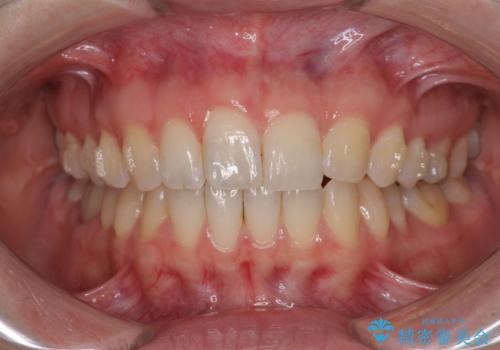

気になる上の歯を改善 インビザライン矯正

- 矯正治療の後戻りが気になるとのことで来院された患者様です。

上顎の後戻りをインビザライン・ライトで治療することとしました。

上顎のみの治療を希望されたため、咬み合わせをしっかりと改善することはできませんでしたが、審美面が大きく改善され、日常生活の機能面でも不具合を感じることはなく、大変満足していただきました。